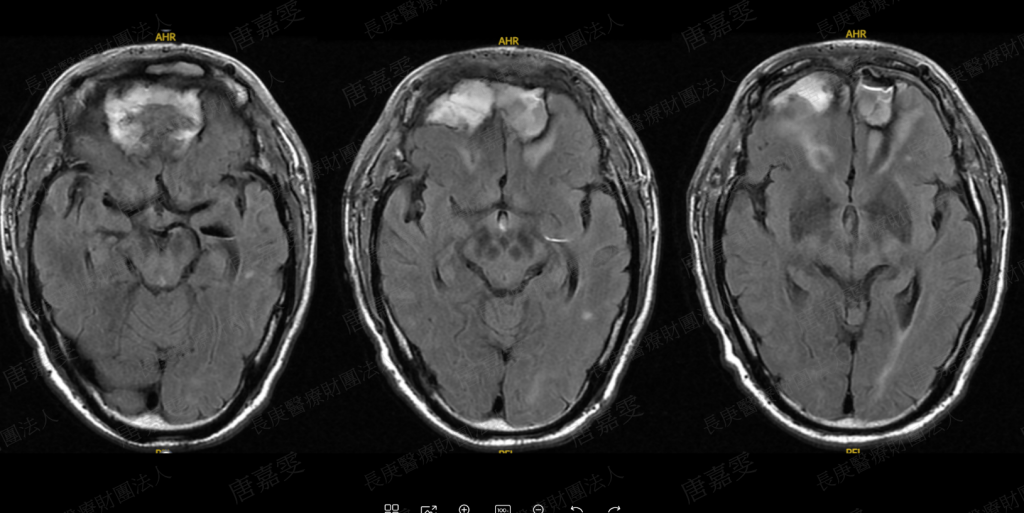

這位病人的治療過程非常漫長且複雜。從簡報中可以看到,病人在不同時間點接受了多次手術,包括鼻竇內視鏡手術、顱骨底清創、腦膿瘍清除,以及VP shunt 與 EVD 的放置與更換。整個病程中總共歷經多次手術與住院,顯示這類感染一旦侵犯到顱內,治療將會非常困難。病人的功能狀態也隨著病程逐漸下降,從原本的生活自理,後來出現癲癇、臥床,甚至最後雙眼失明。

在治療策略上,簡報也提到術後需要定期內視鏡追蹤與清創,並搭配影像學檢查如 MRI 來監測疾病是否有復發或進展。這讓我理解到侵襲性黴菌性鼻竇炎的治療並不是單一次手術就能解決,而是需要長期且密切的追蹤。